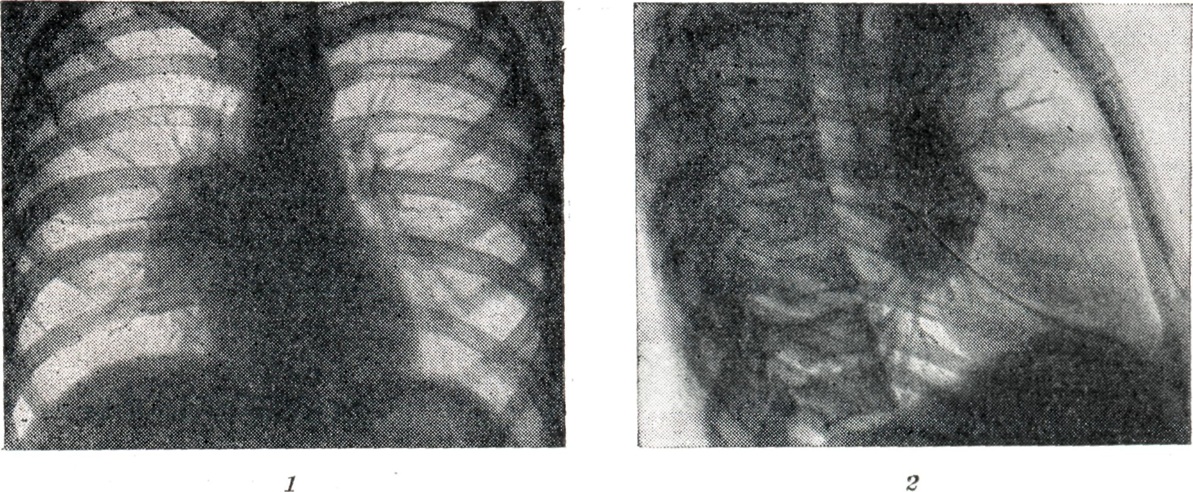

При инфильтративной форме Б. (рис. 4, 1 и 2) возникают воспалительные изменения в лёгочной ткани за капсулой лимф, узлов. Поэтому весь корень или отдельные его участки увеличиваются, тень корня уплотняется. Линия наружного контура корня делается неясной и размытой от воспалительного уплотнения перибронхиальной, периваскулярной и межуточной ткани лёгкого. Опухолевидная и инфильтративная формы Б. при благоприятном течении процесса заканчиваются Рубцовым уплотнением корней лёгких (рис. 5); в отдельных группах лимф, узлов наблюдаются и явления кальцинации (петрификаты): отдельные мелкие плотные тени, иногда сгруппированные в более крупные конгломераты. Дифференцирование сосудистой тени от кальцинатов в лимф, узле проводится при многоосевом просвечивании: тень от петрификата в корне легкого при поворотах исследуемого не выходит за его границы, интенсивность ее не изменяется; тень от осевой проекции сосуда при движении больного вытягивается вначале в овал, а затем в продольную линейную проекцию. Кроме того, тени кальцинированных лимф, узлов редко бывают монолитно плотными и правильной округлой формы с ровными краями, что более характерно для осевых проекций сосудов. При дифференциальной диагностике Б. не следует забывать таких заболеваний, как бронхокарцинома, лимфогранулематоз (см.), лейкемия (см. Лейкозы), застойный корень, бруцеллез (см.), гиперплазия зобной железы, аневризма аорты (см.), лимфосаркома (см.). Прогноз в основном благоприятный, но течение медленное, особенно при формах с большим количеством казеоза и поражением сегментарного или долевого бронха (при образовании свищей). Лечение. В период первичного туберкулёза, когда инфекция в значительной мере генерализована, лечение должно быть направлено на укрепление всего организма с учетом степени вовлечения прилежащих органов и изменений в лёгких. Инфильтративный Б. проходит под влиянием санаторного режима. Режим больного щадящий, и лишь после исчезновения явлений интоксикации и рассасывания гиперплазированных лимф, узлов возможен переход к закаливающему режиму. Интоксикация и гиперплазия лимф, узлов быстрее проходят при применении специфических антибактериальных препаратов: изониазида (тубазид), ПАСК, стрептомицина. Как правило, назначаются сразу два препарата (для предупреждения развития лекарственной устойчивости микобактерий туберкулёза): стрептомицин + ПАСК или тубазид + ПАСК. Суточная доза стрептомицина для взрослых 0,5—1 г, тубазида 0,3—0,6 г, ПАСК 9 — 12 г. Курс лечения ок.6 мес. Казеозные Б. требуют длительного лечения в стационаре. Основной метод лечения — специфическая химиотерапия. В казеозные массы, лишенные сосудов и окружённые фиброзной капсулой, антибактериальные препараты проникают в малом количестве; сравнительно лучше других в казеозные массы проникает пиразинамид. Необходимо применять максимально переносимые дозы препаратов и лечение продолжать в течение многих месяцев (иногда больше года) без перерыва. Курс химиотерапии в 2—3 мес. снижает острые явления заболевания, но не предупреждает новой вспышки. Антибактериальные препараты действуют на казеозный процесс в лимф, узлах медленно, предотвращая вспышку процесса в лёгких или менингеальных оболочках. Известны случаи хирургического лечения Б. путём удаления казеозно изменённых внутригрудных лимф, узлов. Индуративный Б. также медленно поддаётся действию специфических антибактериальных препаратов, к-рые в процессе лечения комбинируются с различными стимуляторами, в первую очередь туберкулином, способным усилить воспалительную реакцию фиброзной ткани и казеоза. При применении антибактериальных препаратов отно-сительно быстро удаётся преодолеть обострение, для полного же излечения необходим значительный срок и комбинация различных методов лечения. Профилактика — см. Туберкулёз. См. также Туберкулёз органов дыхания.